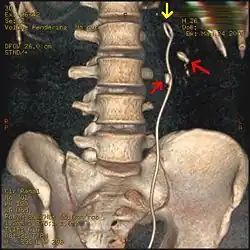

Imaging studies

Calcium-containing stones are relatively radiodense (opaque to X-rays), and they can often be detected by a traditional radiography of the abdomen that includes the kidneys, ureters, and bladder (KUB film).[59] KUB radiography, although useful in monitoring size of stone or passage of stone in stone formers, might not be useful in the acute setting due to low sensitivity.[60] Some 60% of all renal stones are radiopaque.[61][62] In general, calcium phosphate stones have the greatest density, followed by calcium oxalate and magnesium ammonium phosphate stones. Cystine calculi are only faintly radiodense, while uric acid stones are usually entirely radiolucent.[63]

Otherwise a noncontrast helical CT scan with 5 millimeters (0.2 in) sections is the diagnostic method to use to detect kidney stones and confirm the diagnosis of kidney stone disease.[16][57][61][66][7] Near all stones are detectable on CT scans with the exception of those composed of certain drug residues in the urine,[59] such as from indinavir.

Where a CT scan is unavailable, an intravenous pyelogram may be performed to help confirm the diagnosis of urolithiasis. This involves intravenous injection of a contrast agent followed by a KUB film. Uroliths present in the kidneys, ureters, or bladder may be better defined by the use of this contrast agent. Stones can also be detected by a retrograde pyelogram, where a similar contrast agent is injected directly into the distal ostium of the ureter (where the ureter terminates as it enters the bladder).[61]